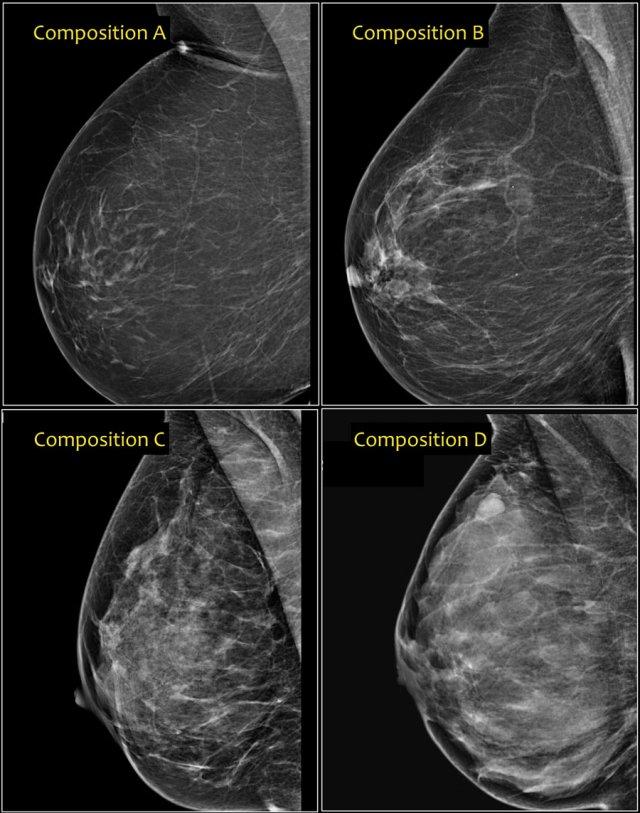

Thành phần Tuyến vú

Trong phiên bản BI-RADS 2003, việc phân loại thành phần tuyến vú dựa trên mật độ tổng thể, chia thành các nhóm ACR: nhóm 1 (<25% mô tuyến xơ), nhóm 2 (25-50%), nhóm 3 (50-75%) và nhóm 4 (>75%).

Trong BI-RADS 2013, việc sử dụng tỷ lệ phần trăm không được khuyến khích, vì trong từng trường hợp cụ thể, điều quan trọng hơn là đánh giá khả năng một khối có thể bị che khuất bởi mô tuyến xơ, thay vì dùng tỷ lệ phần trăm mật độ vú như một chỉ số nguy cơ ung thư vú.

Trong phiên bản BI-RADS 2013, phân loại thành phần tuyến vú được thay đổi thành các nhóm a, b, c và d kèm theo mô tả:

- a– Tuyến vú gần như hoàn toàn là mô mỡ.

Nhũ ảnh có độ nhạy cao trong trường hợp này. - b– Có các vùng mô tuyến xơ rải rác.

Thuật ngữ “mật độ” mô tả mức độ suy giảm tia X của mô vú, không phải các tổn thương nhũ ảnh riêng biệt. - c– Tuyến vú có mật độ không đồng nhất, có thể che khuất các khối nhỏ.

Một số vùng trong tuyến vú có mật độ đủ cao để che khuất các khối nhỏ. -

d

– Tuyến vú có mật độ rất cao, làm giảm độ nhạy của nhũ ảnh.

Lưu ý ở ví dụ bên trái, thành phần tuyến vú được phân loại là c – mật độ không đồng nhất, mặc dù thể tích mô tuyến xơ chiếm dưới 50%.

Mô tuyến xơ ở phần trên có mật độ đủ cao để che khuất các khối nhỏ.

Do đó được phân loại là c, vì các khối nhỏ có thể bị che khuất.

Theo phân loại cũ, trường hợp này sẽ được gọi là ACR 2: mật độ 25-50%.

Ví dụ bên phải có hơn 50% mô tuyến và cũng được phân loại là thành phần c.